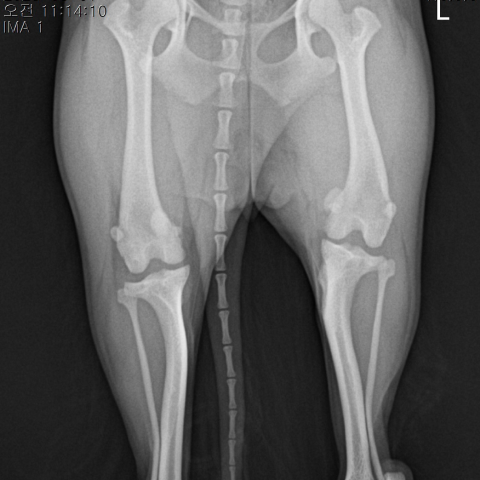

슬개골 탈구

미끄러운 바닥과 두발서기 때문에 슬개골 탈구가 생긴다고 많이들 생각하세요. 하지만 대부분의 슬개골 탈구는 유전성 질환이에요.

증상이 2주 이상 지속 되는 1, 2단계 슬개골 탈구이거나 증상의 유무와 상관없이 3, 4단계 슬개골 탈구로 진행된 경우 바로 수술을 해야돼요. 하지만 증상이 없는 1,2단계의 슬개골 탈구는 나이와 진행 속도 등을 고려하여 수술 여부를 판단하죠.

마사지나 보호대, 보조기 등은 치료 수단이 될 수 없어요. 슬개골 탈구를 교정할 수 있는 방법은 수술뿐이에요.

증상이 없는 1,2단계의 슬개골 탈구라면, 과격한 운동을 줄이고 체중을 조절하여 탈구의 진행을 늦춰주세요.

슬개골 탈구를 교정하기 위해선 여러 가지 수술 기법이 동시에 적용돼요. 가장 중요한 건 아이의 무릎 상태에 맞는 적절한 수술 기법이 최소한으로 적용되어야 한다는 거예요. 그래야만 앞으로 남은 긴 견생을 만성 관절염으로 고생하지 않고 행복하게 지낼 수 있죠. 최적화 수술로 만성 관절염을 최소화하는 것. 그것이 빌리브의 슬개골 탈구 수술입니다.

슬개골 탈구 수술 전

슬개골 탈구 수술 후